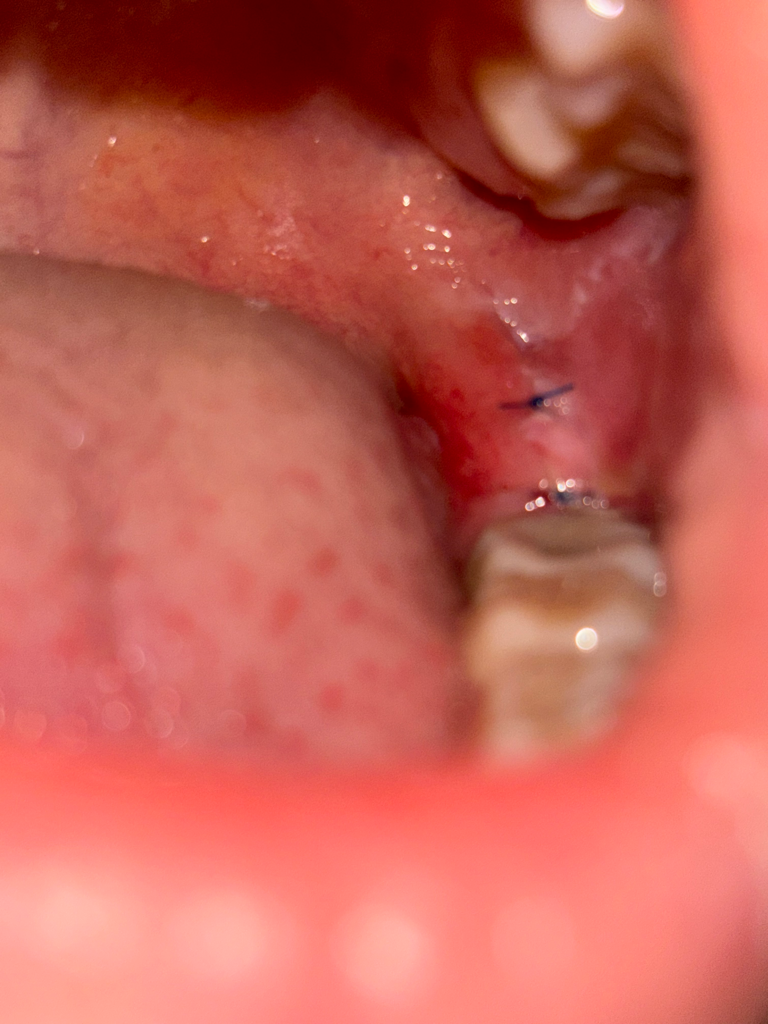

매복 사랑니 발치 후 잇몸 부음

매복사랑니를 뽑은지 3일차인데 잇몸이 많이 붓는듯한 느낌이

들고 상악 잇몸 쪽 까지 하얗게 구내염같은게 올라왔어요.

혹시 드라이소켓은 아니겠죠? 설날이라 치과가 휴무라 걱정이 많이 들어서요....

안녕하세요. 김지훈 치과의사입니다.드라이 소켓이 아니며 하얗게 올라오면서 세포가 차오르는 것이 정상적인 회복과정입니다.

드라이 소켓은 아니신거 같고, 사랑니 발치를 하고 나서 잇몸이 아직 아물지 않아서 그런거니 너무 걱정하지 않으셔도 될것같습니다.

사랑니를 발치하고 잘 봉합이 되어 있어서 잘 아물고 있는 것으로 보입니다.

발치를 하고 3일 정도까지는 발치한 부에 통증이 있을 수 있기 때문에 해당 부위가 자극되지 않도록 하는 것이 좋습니다.

현재로선 드라이소켓의 가능성은 높지 않아 보입니다. 발치 후 주의사항 잘 지키고 처방된 약 잘 복용하시면 크게 문제 없을 것 같습니다.

사랑니 발치후에 1-2주간은 붓기 및 통증이 나타날수 있습니다. 현재 사진상크게 문제가 되지는 않으며, 통증이 있는 경우 소염진통제를 복용하길 권합니다.